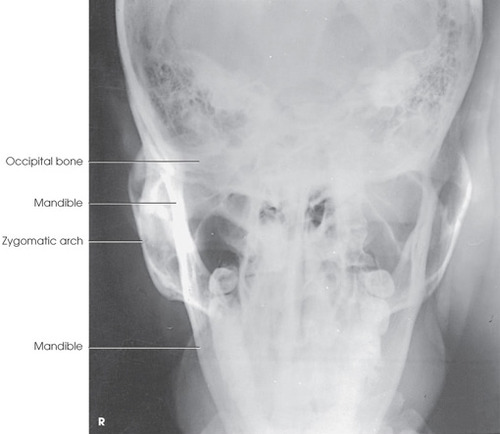

AP Axial (Modified Towne) for Zygomatic Arches

Part Position: Back of head on IR; OML or IOML perpendicular.

Central Ray: 30° caudad to OML (or 37° to IOML), entering 1 inch above nasion.

Collimation: 3×8 c/w